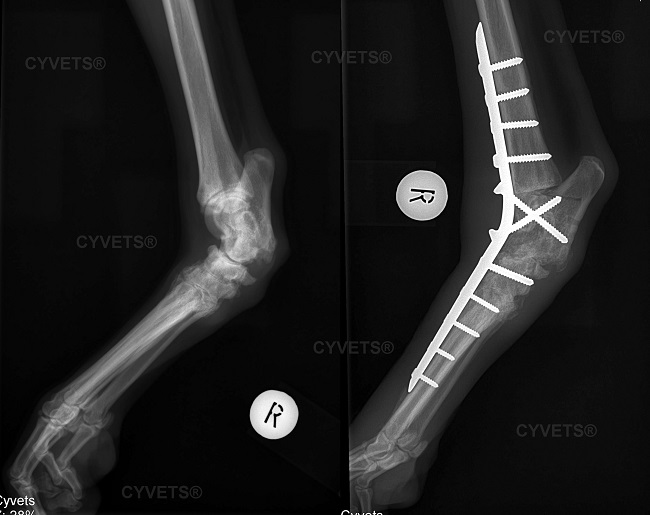

Pantarsal arthrodesis

Pantarsal arthrodesis includes the fusion of the tarsal joint (hock joint) with the use of a plate, screws and bone tissue that is harvested from another location.

It is performed in cases of severe injuries, end stage arthritis and standing deformities of the hock joint.